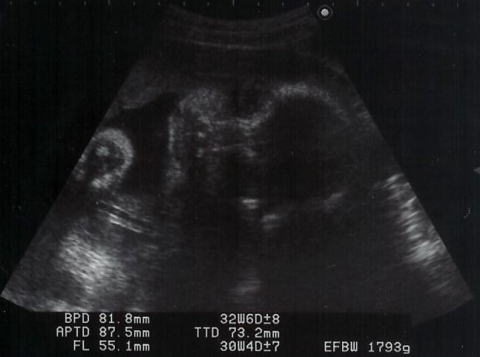

|  shigeru、3週間ぶりの健診です。ママは後期の検査がありました。ここのところ、ママは夜眠れない日々が続いています。そのことをお医者様に話したら・・・「(shigeru)重さは1793g。重くなったんだもの、眠れないのは仕方ないですよ。」と。ママは眠いときに眠れば、夜に眠れなくても大丈夫とのこと。お医者様は「かわいいわね〜」とエコーをみながら言いましたが、ママには骸骨か宇宙人にしかみえません。でも、shigeruは大きくなりましたね。ほっぺがふっくらしているのがエコーでもわかるのですから。

右が頭で足を抱えて下を向いてます。

顔面アップ。右が頭で、こちらを向いています。